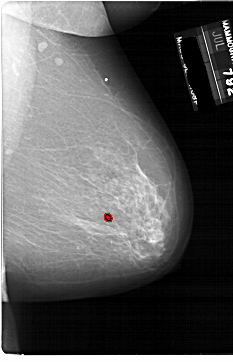

A_1861_1.RIGHT_CC

RIGHT_CC LINES 6871 PIXELS_PER_LINE 4051 BITS_PER_PIXEL 12 RESOLUTION 43.5 OVERLAY

FILE: A_1861_1.RIGHT_CC.OVERLAY

TOTAL_ABNORMALITIES 1

ABNORMALITY 1

LESION_TYPE CALCIFICATION TYPE PLEOMORPHIC DISTRIBUTION CLUSTERED

ASSESSMENT 4

SUBTLETY 2

PATHOLOGY BENIGN

TOTAL_OUTLINES 1

BOUNDARY